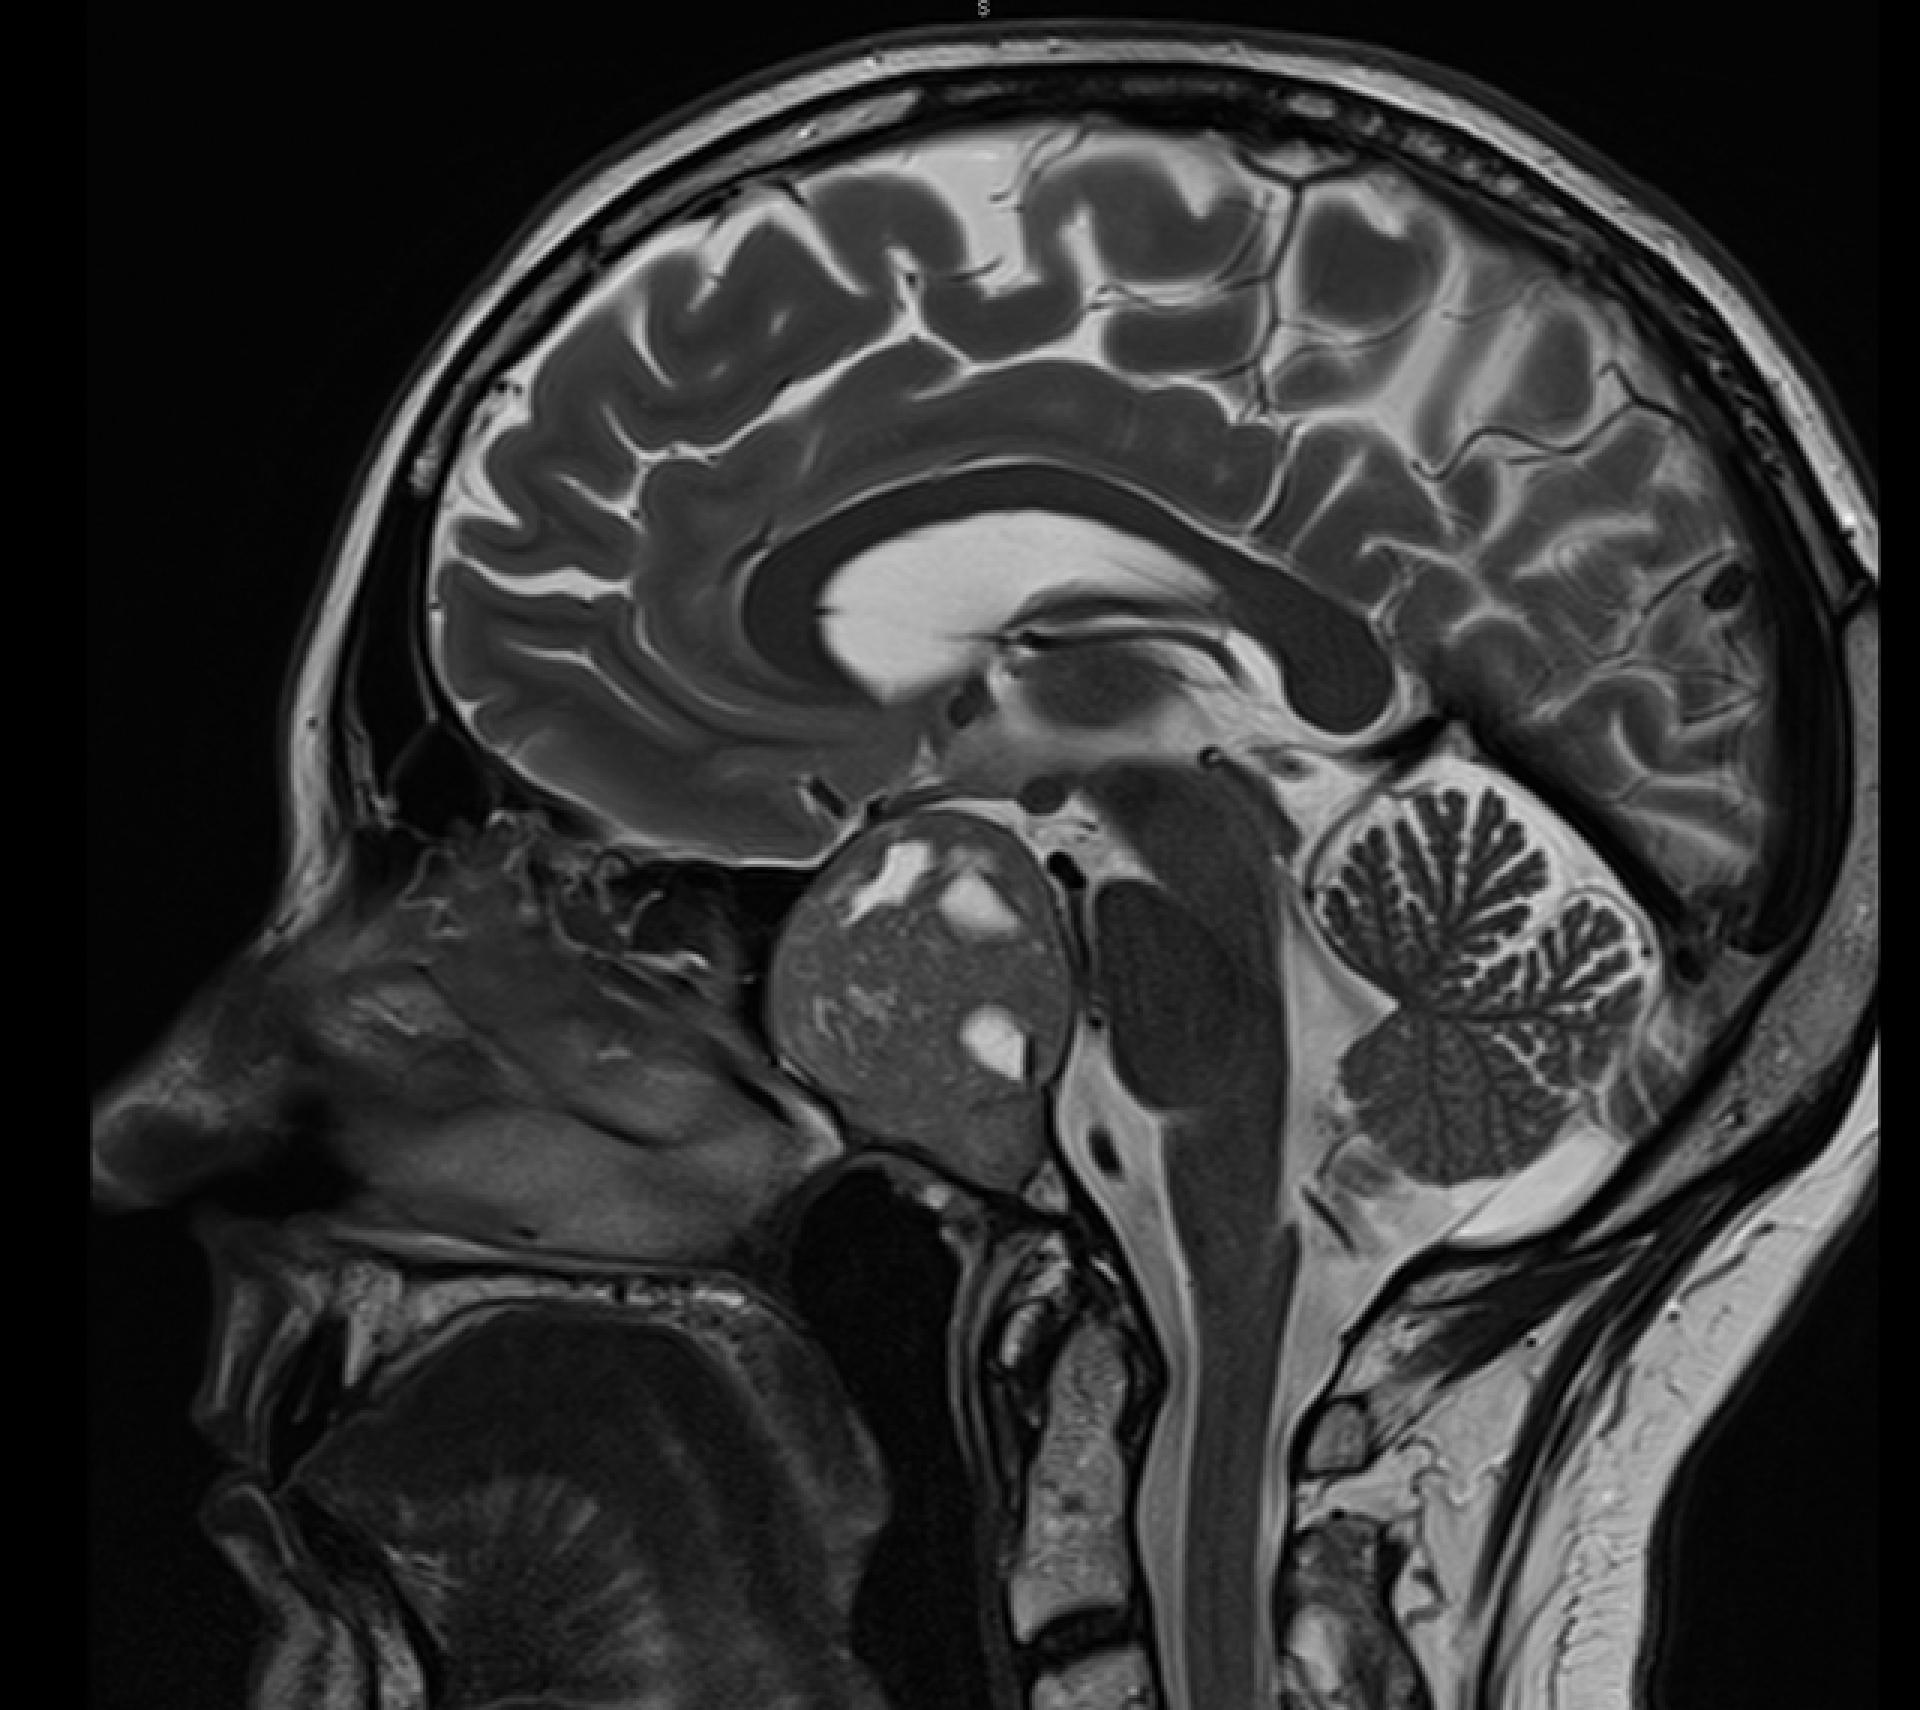

une IRM hypophysaire, examen de référence pour localiser la tumeur et évaluer ses rapports avec le chiasma optique ;